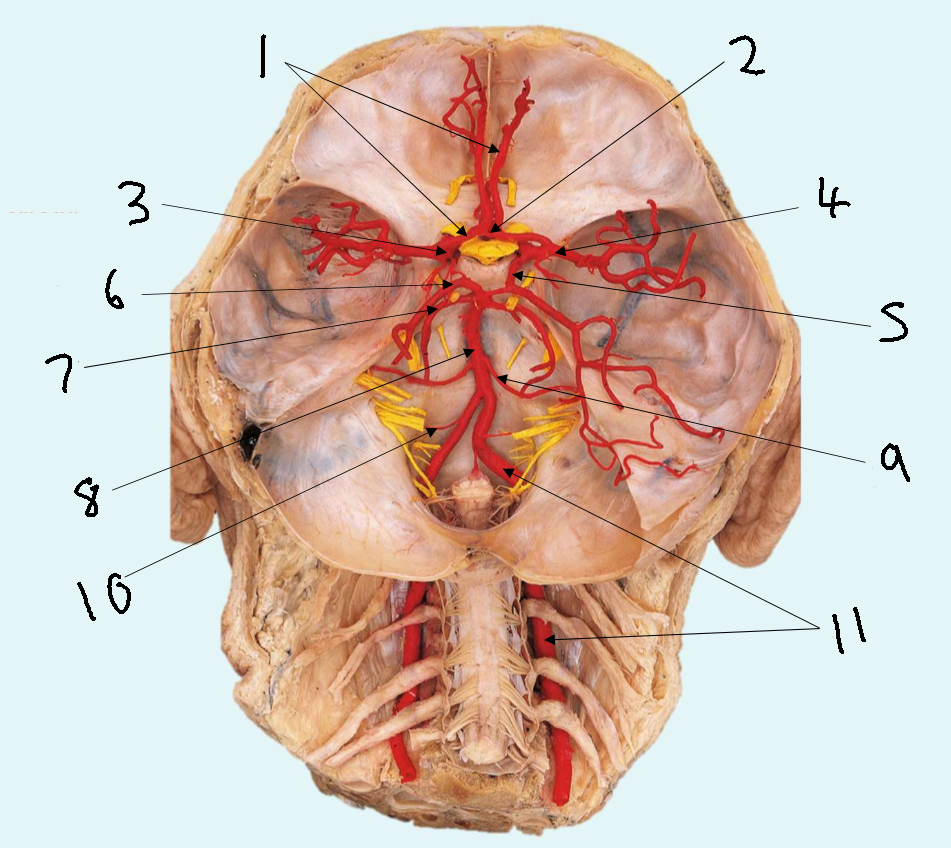

What is 1?

anterior communicating artery

What is 2?

anterior cerebral artery

What is 3?

middle cerebral artery

What is 4?

internal carotid artery

What is 5?

posterior communicating artery

What is 6?

posterior cerebral artery

What is 7?

superior cerebellar artery

What is 8?

pontine arteries

What is 9?

basilar artery

What is 10?

anterior inferior cerebellar artery

What is 11?

vertebral artery

What is 12?

posterior inferior cerebellar artery